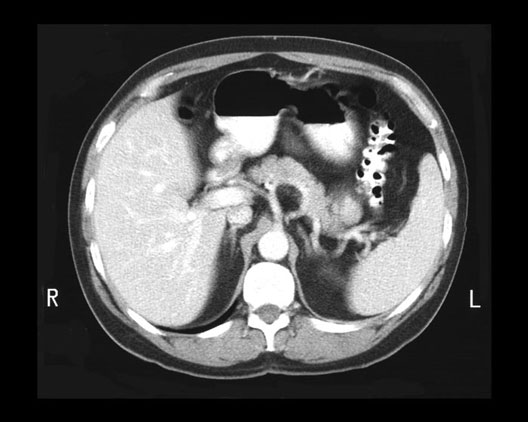

Celiac Artery

1. Liver

2. Stomach

3. Colon

4. Celiac Artery

5. Spleen

6. Aorta

7. Verterbral Body

8. Spinous Process of vertebra

9. Right crus of diaphragm